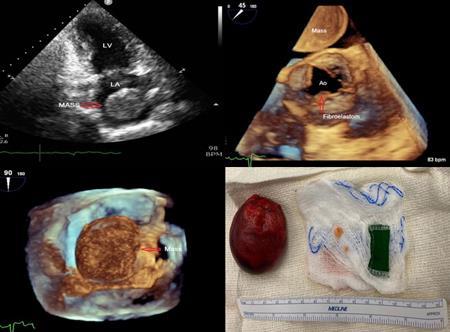

LARYNGEAL SYNOVIAL SARCOMA THAT METASTASIZED TO THE HEART

Christopher N. Matthews1 , Syed Farrukh Mustafa1 , Sidra Salman1 , Akshaya

Gopalakrishnan1, James Salonia1 , Deepika Misra1

1Mount Sinai Morningside-West Hospitals, Icahn School of Medicine at Mount Sinai, New York, NY, United States

Presented at the American College of Cardiology (ACC) Annual Meeting that was held in New Orleans, Louisiana, United States from March 4-6, 2023.